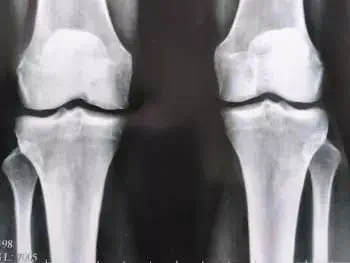

ȚINEȚI MINTE: ARTRITA ȘI ARTROZA DISTRUG ȚESUTUL CARTILAJULUI ÎN 3 ANI! Din păcate, nu există medicamente pentru artroză, doar operația vă va ajuta…

img

Efectul artrozei asupra țesutului cartilaginos al articulației genunchiului.

Din păcate, doctorul avea dreptate...După 2 luni, a fost insuportabil de dureros să mă ridic în picioare, medicamentele și analgezicele au încetat să mă ajute, deși am aruncat mulți bani pe ele, iar medicamentele mi-au distrus stomacul și ficatul - a trebuit să renunț la medicamente! A trebuit să cumpăr un scaun cu rotile și așa să mă mișc prin apartament... Doctorul a spus că în 3 ani osteoartrita distruge țesutul cartilaginos, dar văd că a început mult mai devreme, cel mai interesant lucru este că simțeam durere în articulații, și apoi într-un fel totul s-a schimbat brusc, și m-am găsit într-un scaun cu rotile, fără speranță de recuperare, după cum îmi amintesc, lacrimile se rostogoleau, și aceasta a fost cea mai groaznică perioadă din viața mea.…..